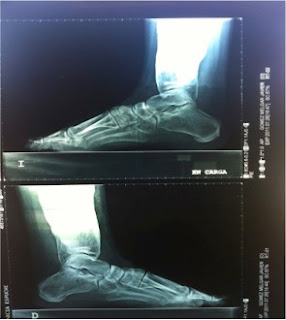

Radiología: se caracteriza por un engrosamiento cortical de la diáfisis de aspecto fusiforme, que puede extenderse y afectar a las metáfisis pero nunca se afectan las epífisis. El canal medular se muestra estrecho

La imagen radiológica típica en los huesos largos aparece en el 94% de los pacientes con mutaciones identificables, un 54% también la presenta en el cráneo y un 63% en la pelvis . A veces, también existe afectación de huesos cortos, como el carpo o las falanges

Radiografía anteroposterior de las manos en la que se aprecia un engrosamiento de los huesos del carpo, de las diáfisis de los metacarpianos y de las falanges de ambas manos.